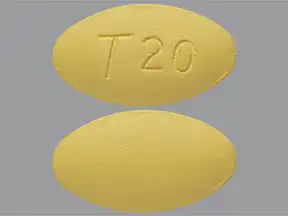

Ésta se produce cuando un varón no puede obtener o mantener una erección firme, adecuada para una actividad sexual satisfactoria. El tadalafilo pertenece a un grupo de medicamentos denominados inhibidores de la fosfodiesterasa tipo 5. El resultado es la mejoría de la función eréctil. Medizzine le recomienda que consulte a su medico si desconoce la razón por la que le ha prescrito tadalafilo. Cubierta pelicular: lactosa monohidrato, hipromelosa, triacetina, dióxido de titanio E, óxido de hierro amarillo E, óxido de hierro rojo E y talco. La composición de las distintas presentaciones puede variar de un país a otro. Este medicamento contiene lactosa.